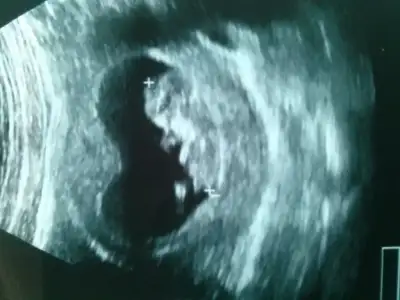

dr soylemeden siz gorun genital nub teorisi ( bebegin cinsiyeti)

Benim bebisin cinsyeti ne olabilir acaba :))

Acaba benim bebegin cinsiyeti nedir sizce arkadaslar bana kiz gibi geldi :))